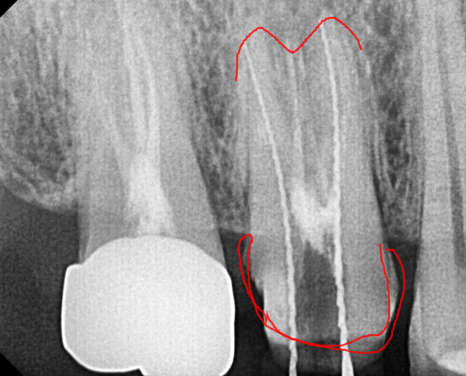

3달이 지나서 다시 하얀색 재료를 채워 넣는 것으로

치료를 마무리했습니다.

x-ray를 봐서는

염증이 없어진건지 잘 모르시겠죠~?

변화가 된 모습만 비교해드릴께요~

뿌리 절반 이상 염증들이

3달의 치료과정을 통해

손톱만큼 줄어들었습니다.

250116

발치 대신 신경치료

치료 시작 9개월 뒤

이제 뿌리 끝 까만 부분

거의 보이지 않습니다.

염증이 남아있으면 제대로 뼈가 차지 않는대요.

깨끗하게 염증이 없어졌기 때문에

까맣게 녹아 버린 뼈가

다시 하얗게 채워진 모습을 볼 수있네요~